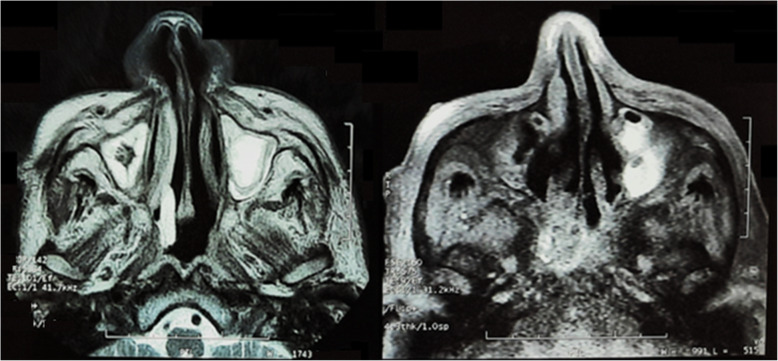

Two weeks post COVID-19, the patient presented with headache, nasal congestion, complete left ophthalmoplegia, complete ptosis, and conjunctival chemosis (Fig. 4A).

Fig. 4.

A Chemosis and total ophthalmoplegia of the left eye. B Red arrow showing proptosis of the left eye along paranasal CT. C Blue arrow pointing to infiltration of soft tissue retro orbit sharing in the presentation of orbital apex syndrome donating invasion from infected and inflamed sinuses. D Blue arrow representing infiltration of periantral fat donating invasion from nearby sinuses

Computed tomography (CT) of the paranasal sinuses without intravenous contrast revealed pan sinusitis much more evident along the left side with obliterated ostiomeatal complex, abnormal fatty stranding surrounding the distal left side optic nerve close to the optic foramen suspicious of orbital cellulitis (Fig. 4).

MRI orbit with contrast revealed diffuse enhancing mucosal thickening with internal fluid level and true diffusion restriction denoting acute sinusitis in the left frontal, ethmoidal, and maxillary sinuses, with left orbital fat diffuse edema with faint enhancement confirming orbital cellulitis.